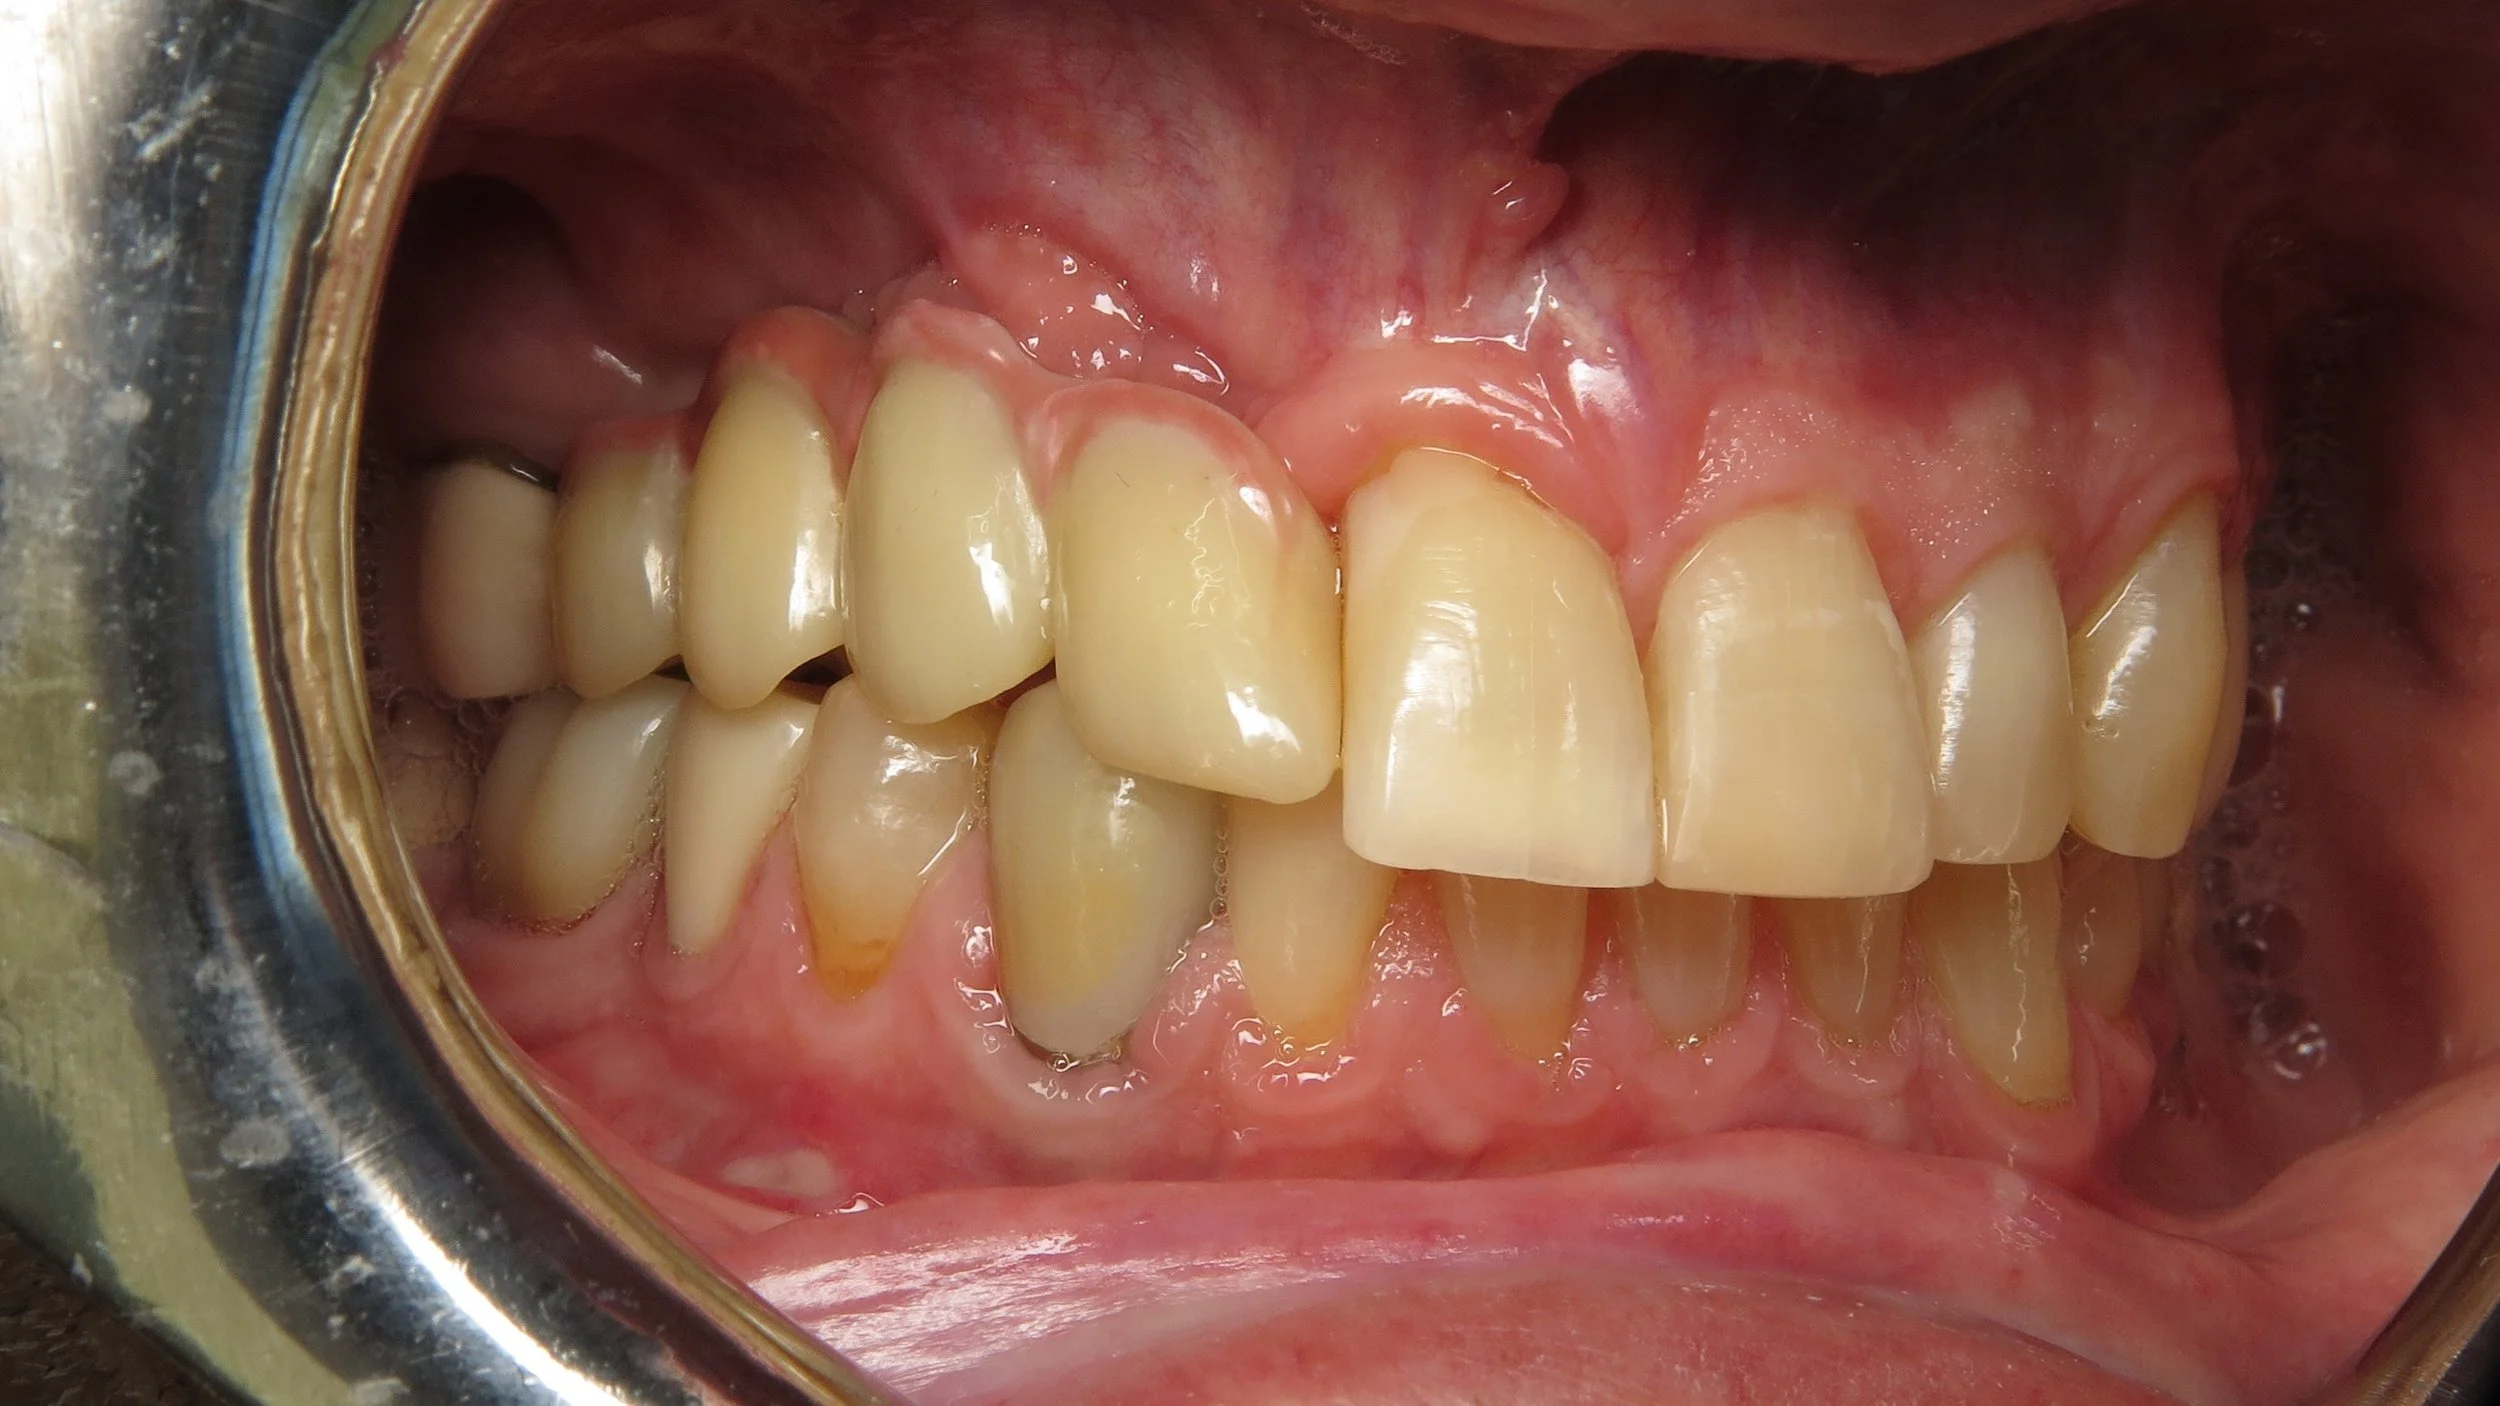

The following cases were done by Dr. Johansen: